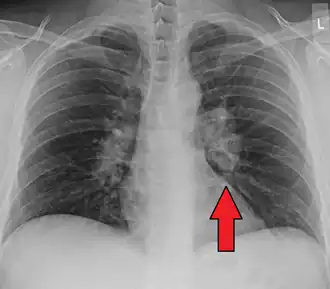

-

Hilar adenopathy especially on the person's left (AP CXR) -

Hilar adenopathy especially on the person's left (lateral CXR) -

Hilar adenopathy especially on the person's left (coronal CT) -

Hilar adenopathy especially on the person's left (transverse CT)